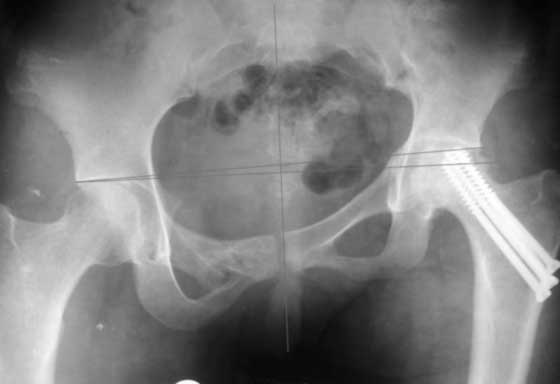

Согласен с Рунковым. Девочка молодая. Имеется ассиметричное расположение вертлужных впадин в прямой проекции. Так как повреждение таза было вертикально-нестабильное, вероятно имеется так же ассиметрия в передне-заднем направлении. Конечно протезом можно компенсировать имеющееся укорочение, но ассиметрично расположенные тазобедренные суставы приведут к нарушению двигательного стереотипа, нарушение походки, остеохондроз и т.д.

До сих пор идут большие дискуссии по поводу высокого центра ротации и единого мнения, насколько я знаю, нет. Компенсация длины, рычагов ягодичных мышц и т.д., а уж при вертикальном смещении таза,влияние его на последующее эндопротезирование просто не узнать (слишком мало наблюдений и много факторов, влияющих на конечный результат). Фото лишний раз подтверждают, укорочение за счет контрактуры.

Привет, Макс. Не торопись, посмотри внимательно на истинную картину. Толстая стрелка указывает на нижний край смещенного кп сочленения.

Поэтому считаю, что Принять какое-либо решение без кт и дополнительных проекций неразумно.

разговоров нет, смещение значимое, какое оно было, такое и осталось. Будут проблемы и с сидением и с осанкой и т.д. Идеальным вариантом было бы, конечно, исправить деформацию, а потом запротезировать. Но... цена вопроса. сейчас деформация, судя по костной мозоли, стабильная, и таз несет основную свою функцию - опорную, явно КПС не болит. Превратить стабильную деформацию в нестабильную и потом ее исправить - задача непростая, но выполнимая. Оперативное лечение будет сложное, скорее всего многоэтапное и длительное. С определенными рисками, общехирургическими и специфическими, например несращение зоны остеотомий - нестабильный таз, ризидуальное смещение (в пределах 1 см вполне вероятно). Если считать, что на тазе укорочение см 3, остальные 5. все-таки сгибательно-приводящая контрактура. На протезе от контрактуры можно избавиться, да и см 2 удлинить за счет опила, головки. В такой ситуации решение должна принять пациентка и оно должно быть действительно информированным.